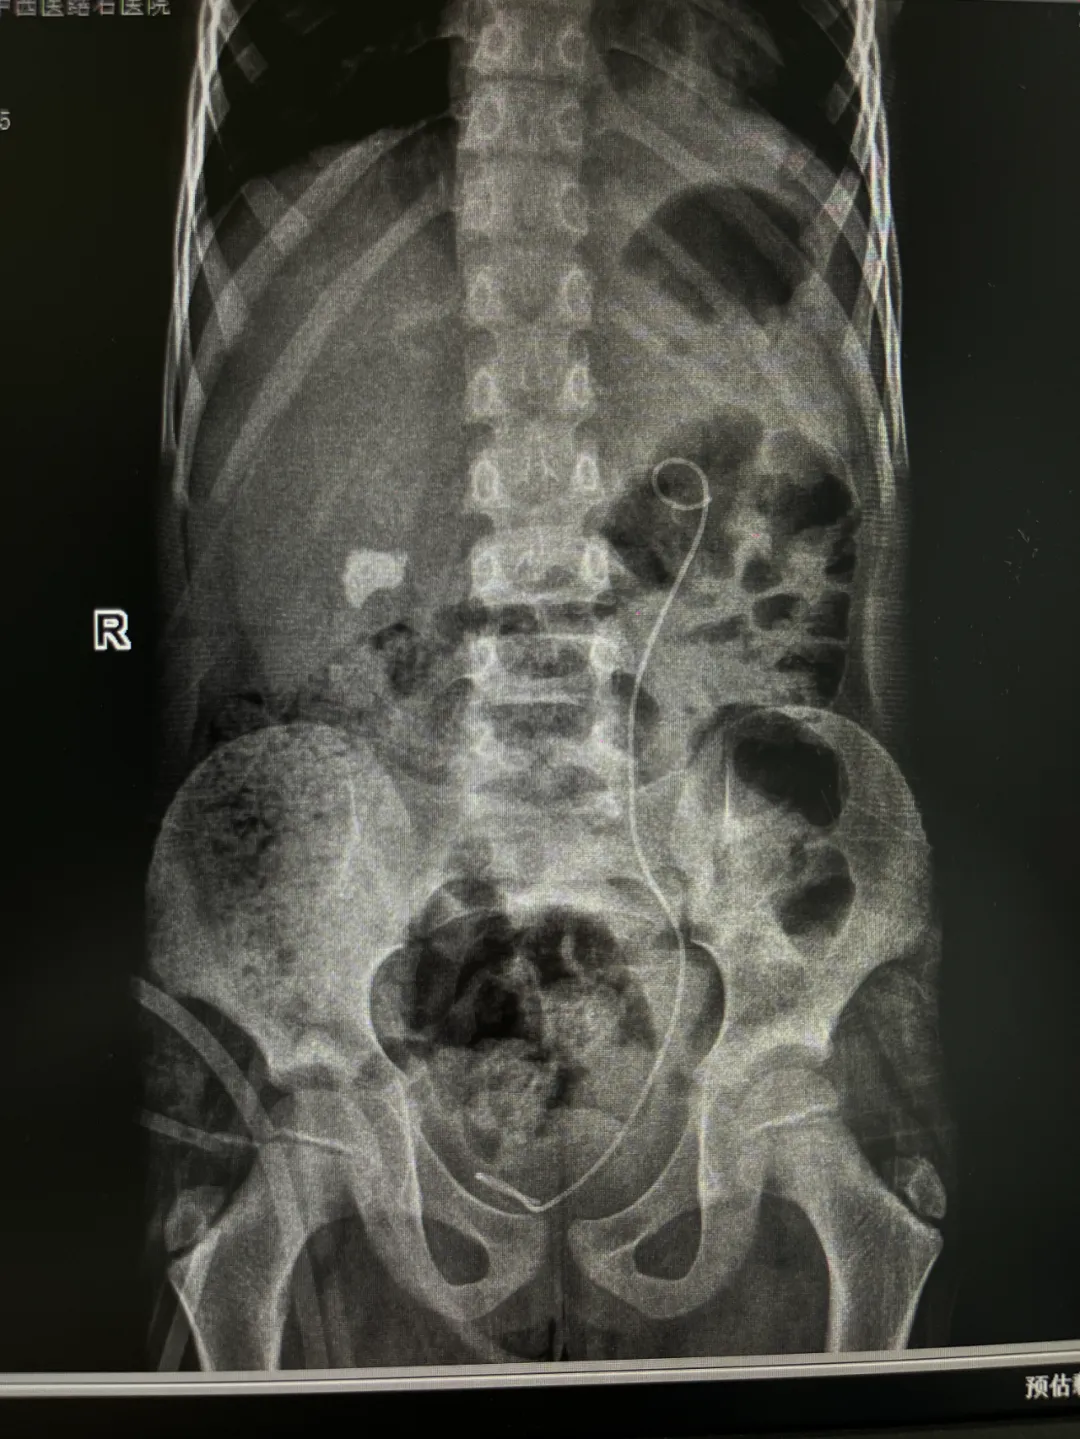

不久前,7 岁的小谢因双肾结石引发肾积水、尿路感染,辗转多家医院后,来我院求得进一步治疗。 两颗大结石,形成了梗阻! 微创手术化解危机 近日,一名7岁的小患者因“双肾结石并积水和感染”来我院就诊,收住院后,泌尿外科医生结合患者病情制定微创手术(分两期完成)治疗方案。待患儿感染控制后分别在全麻下行微创碎石取石手术,于近日进行了第一期手术,手术过程顺利。 手术由院长亲自指导、泌尿外科医师主刀,采用微创碎石取石术——该微创方式更契合儿童器官娇嫩的生理特点,能减少对身体的干扰,无需腹部切口,仅通过尿道、膀胱进入输尿管,通过微创方式将结石处理后取出,再用取石网篮将碎石取出。 由于儿童输尿管管腔狭窄,手术操作难度更大,外科主任团队凭借多年治疗儿童泌尿系疾病的经验,小心翼翼地操控器械,仅用40分钟就顺利清除了左肾结石,对梗阻问题开展针对性干预,这也为为后续诊疗步骤奠定基础;对于右侧肾内的结石,则是择期进行手术。 ▲一期手术完成后的影像检查 术后小结! “儿童肾结石不像成人那么常见,但一旦发生,若合并梗阻、感染,可能对发育中的肾脏造成不可逆损伤。”主治医师在术后科普中提醒,儿童肾结石多与饮水不足、饮食结构失衡、代谢异常等因素相关,家长日常要注意让孩子多喝白开水(每日饮水量建议 1500-2000ml),少喝含糖饮料,避免过量食用菠菜、巧克力、坚果等草酸含量高的食物,定期体检时可关注泌尿系超声检查,做到早发现、早干预。 此次为小谢成功诊疗,是我院儿科与泌尿外科多学科协作的又一次实践。多年来,我院始终坚持 “以患者为中心”,通过微创手术、个体化方案,长期为低龄患儿的结石、梗阻等泌尿系问题提供诊疗服务,用精准医疗守护儿童泌尿健康,始终以 “患儿为中心” 优化诊疗服务流程。未来,我院将持续提升儿童专科诊疗能力,为更多患病儿童筑起健康屏障。▲影像检查显示:小谢双侧输尿管内竟卡着